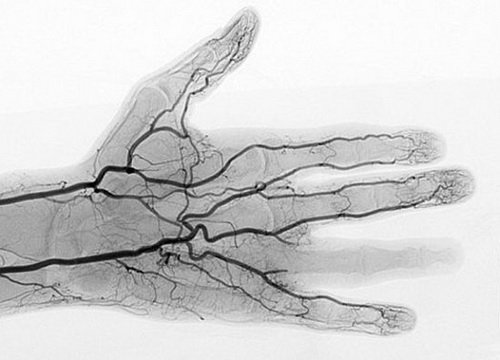

2、X光血管成像术

X光血管成像术让手上如此细小的血管都呈现出来。由这种最新数码探测仪生成的图像质量可以让放射科医师不用使用高剂量辐射物,也能看清楚器官的细微之处。这张照片显示了手外伤的直接影响——没有血液流向第四根手指,而其他手指的小血管却清晰可见。